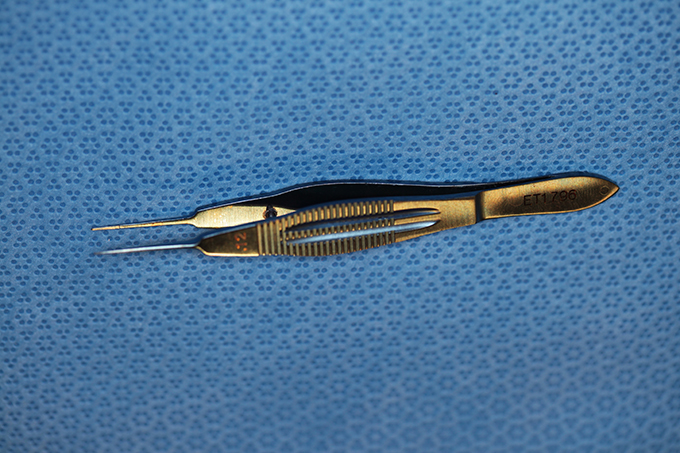

Bonn Forcep .12 Teeth

(aka Bonn Forceps)

catalog number: Storz E1809

Typical Use(s): Holding delicate tissue such as a scleral flap during glaucoma surgery; Has fine teeth smaller than classic .12 forceps